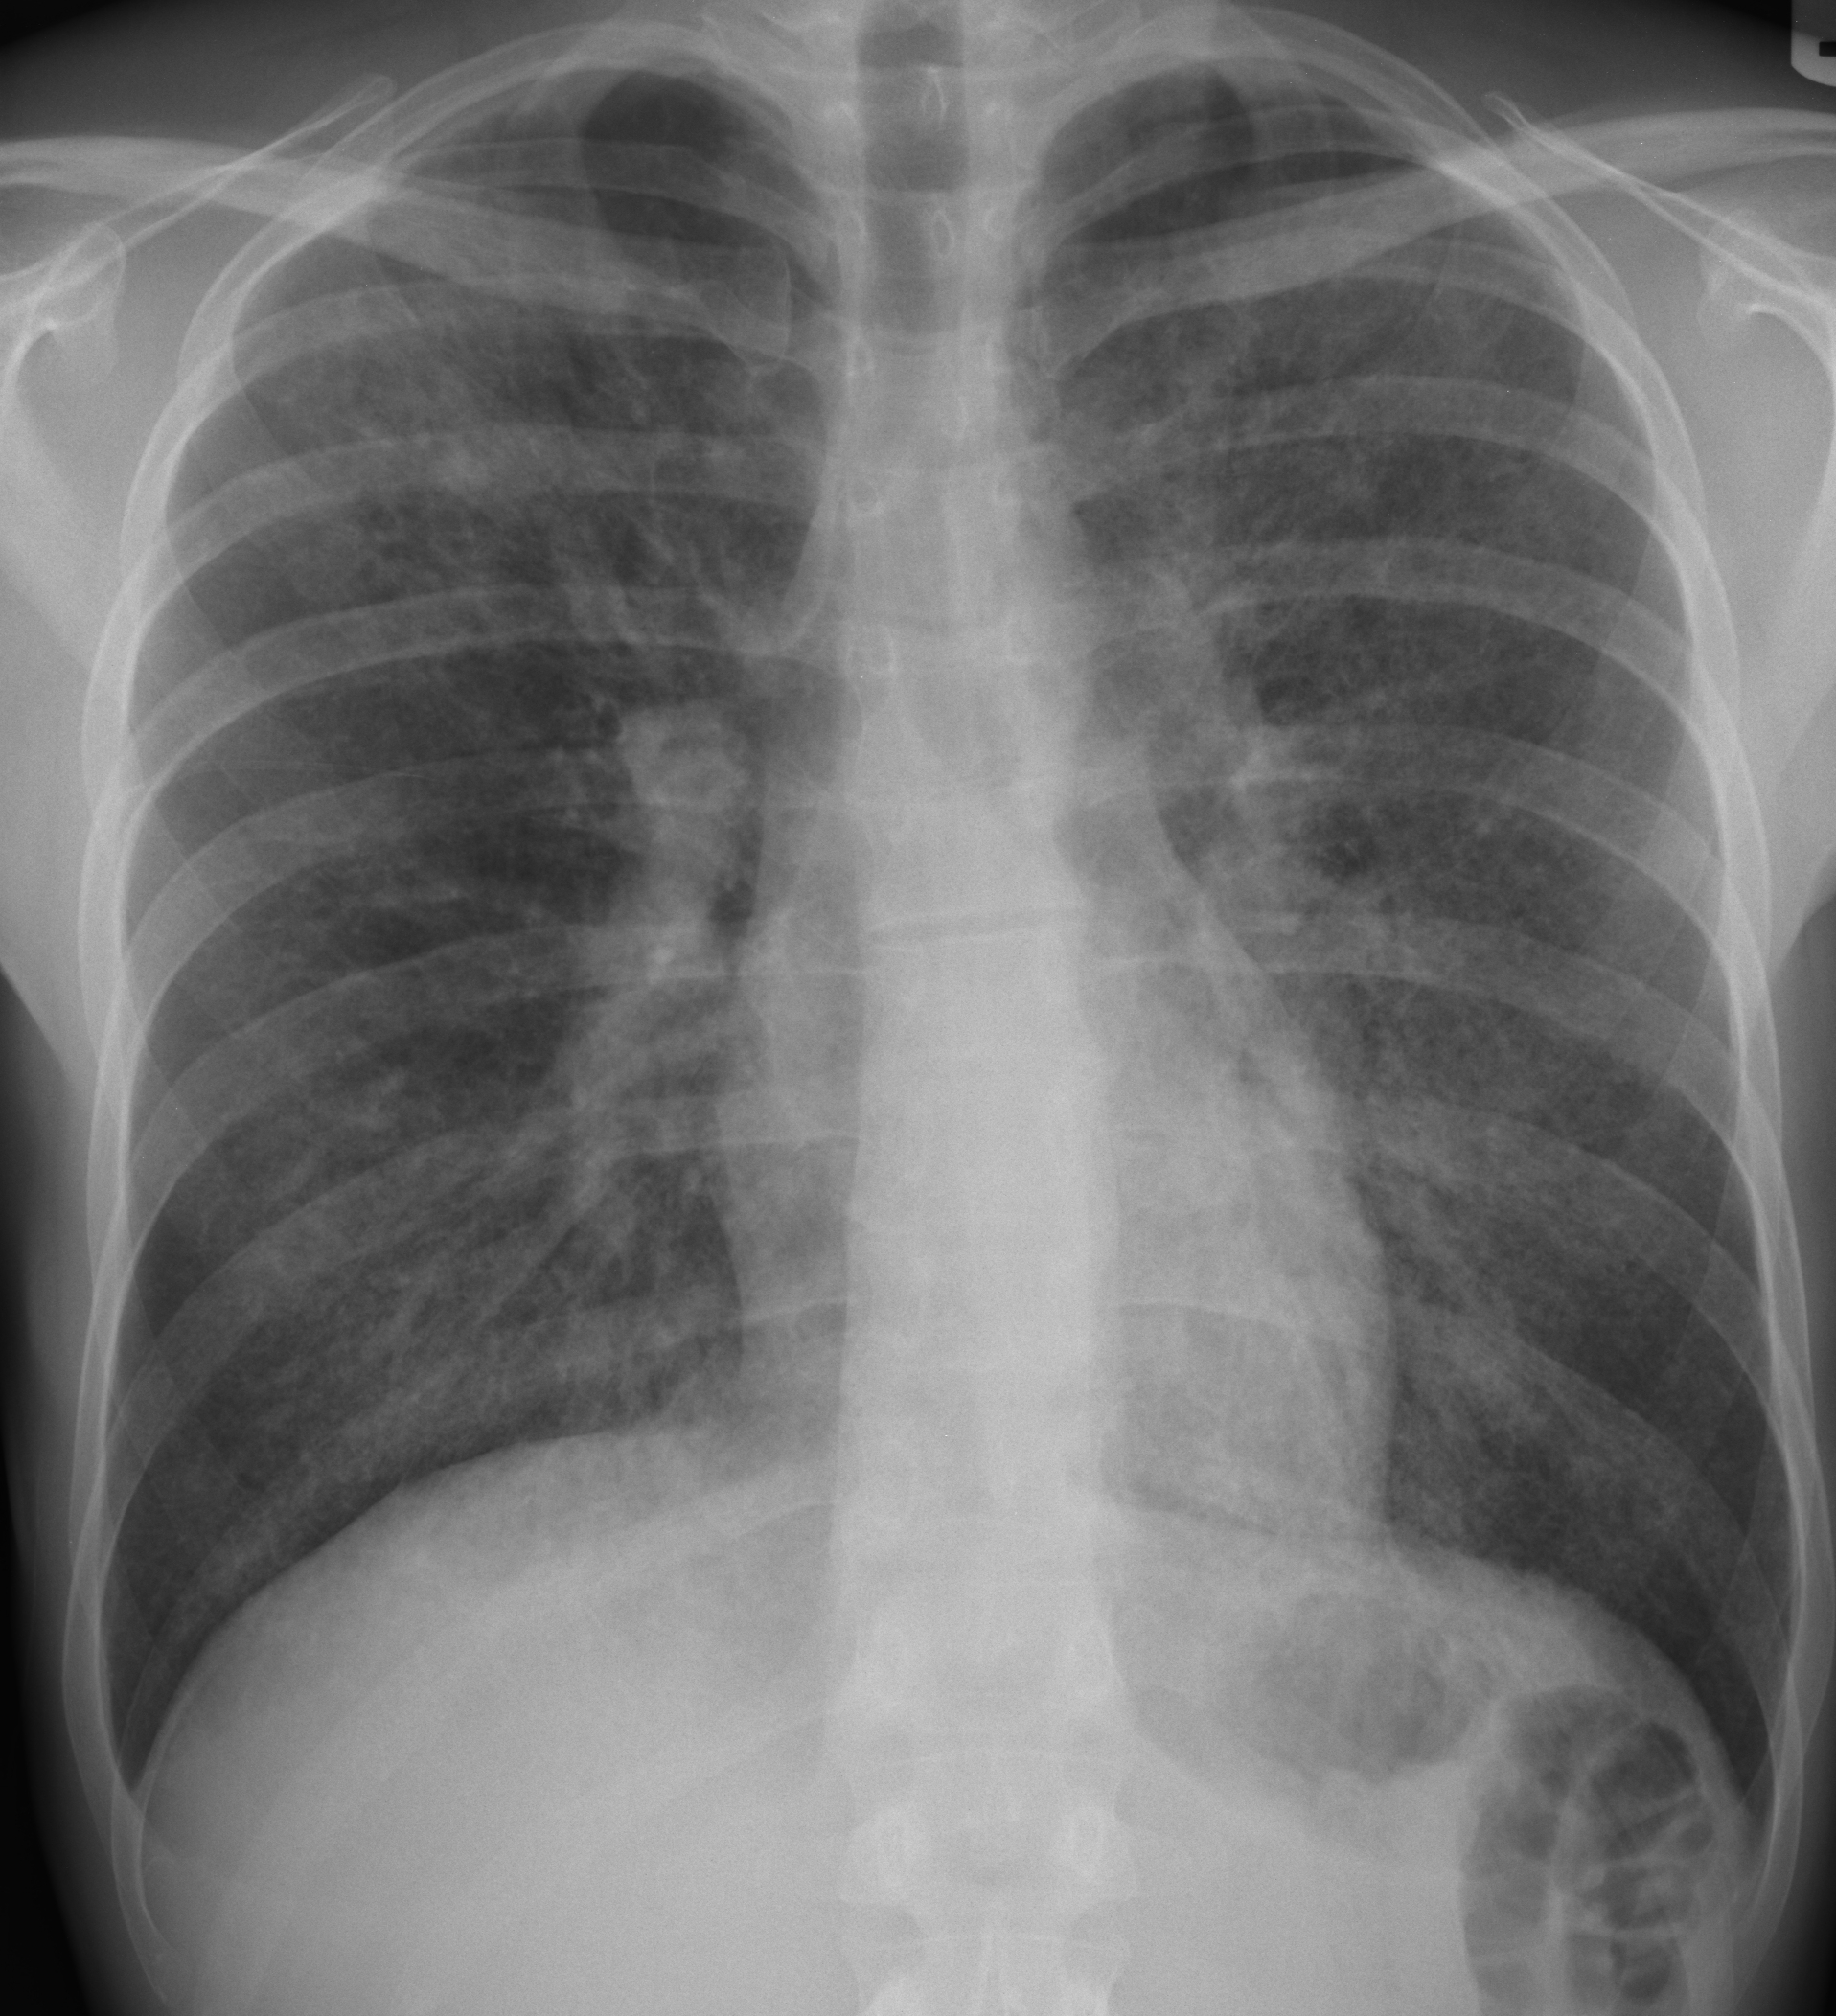

Patient presents with fever, fatigue, and shortness of breath. Chest auscultation reveals mild crackles in lower lobes. No signs of cyanosis. Patient is alert and oriented.